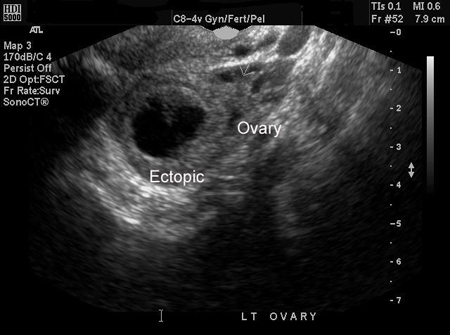

[Figure caption and citation for the preceding image starts]: Imagen de ultrasonido de embarazo ectópicoDe la colección de la Dra. Melissa Fries; usado con permiso [Citation ends].